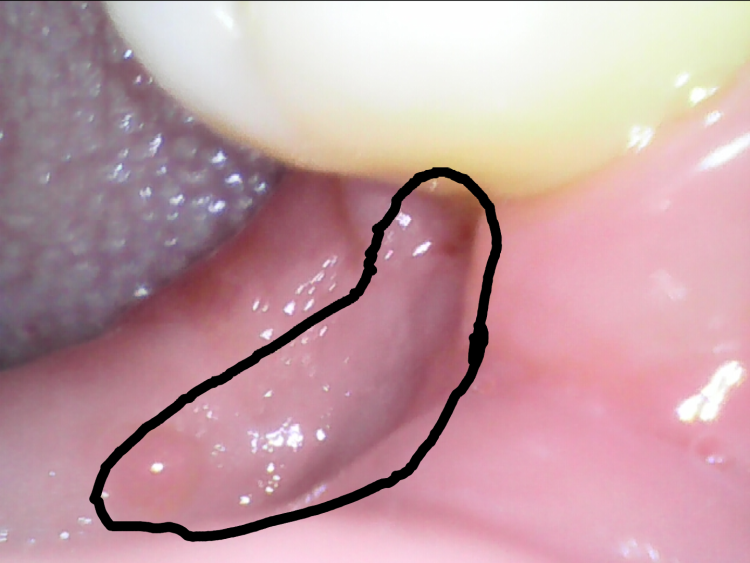

매복사랑니 발치후 두달차. 구멍,불편감 사진있습니다.

발치후 부터 지금까지 사진과 같습니다

발치부위 잇몸이 매꿔지질 않습니다.

비어있는 느낌이 24시간 들고

음식물이 너무 잘낍니다

사진처럼 빨갛게 파여있는 병변 부분도있고

다른 사람들은 평평하게 잇몸살이 차오르는데

저는 안쪽잇몸과 바깥쪽 잇몸이 분리된느낌입니다

말표현이 이상한데 사진보시면 이해하실겁니다

아무리 생각해도 잇몸이 평평하게 차오를것 같지않습니다.

발치후부터 두달이 넘는기간동안 똑같은 상태입니다

• 1번 째 사진

• 2번 째 사진

• 3번 째 사진